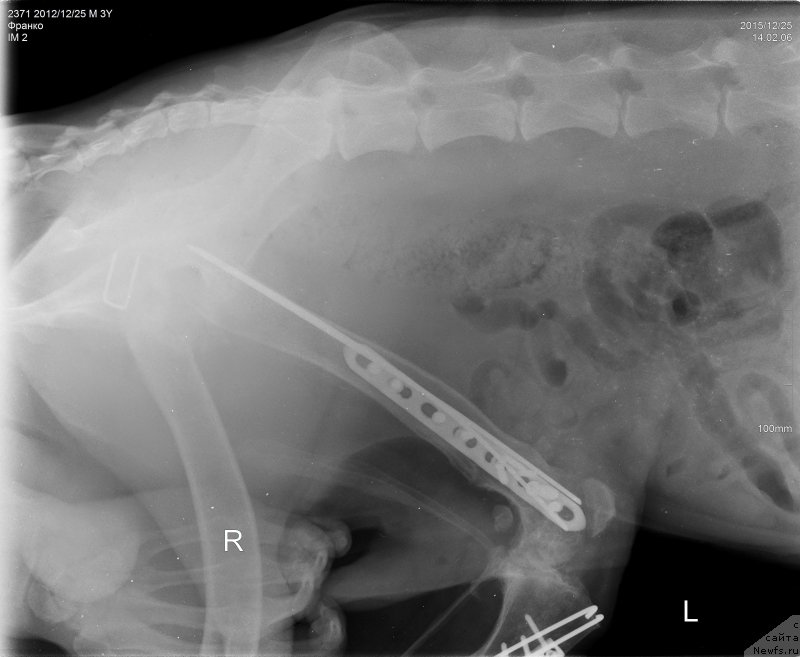

2015.12.25.=Франко снимки бедро латер

Фотография № 198290

2015.12.25.=Франко снимки голень

Фотография № 198291

Сергей Александрович написал что абсцесс в мягких тканях а не в надкостнице, как нам озвучили на рентгене.

Ну и артроз коленного сустава.

Назначил дополнительно к выписанному препарату гиалутидин и превикокс 227 по 1.5 таблетки в день на 8 месяцев , и хирург, ставивший катетор в лапу, чтобы гной выходил тоже сказад

Пластину на голени надо удалять.

Вот что делать?

Артроз у Франко ужаснейший.

Хуже мне кажется уже и быть не может.

Нужно чтоб пластины стояли как можно дольше.